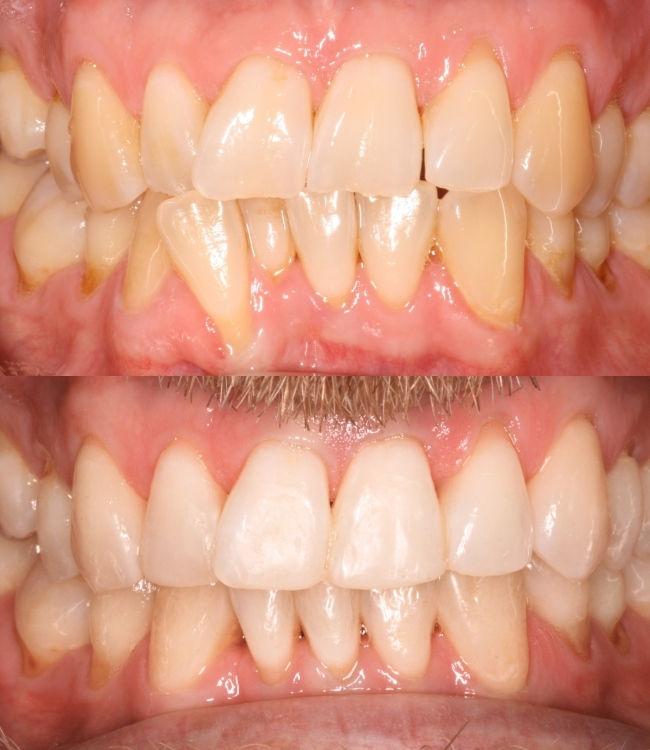

Jonathan came to us wanting to make a change – he had crowding in his lower front teeth and one tooth was pushed forward and twisted, making his smile look uneven.

2. Straightening with Invisalign – With aligners worn as advised, the teeth gently moved into a much straighter, neater position.

3. Whitening for a brighter smile – Professional whitening to give a cleaner, brighter look.

4. Composite bonding to perfect the final look – Added small, precise touches to tidy edges and shapes, creating a smooth, natural finish.

The result? A bright, perfectly balanced smile.

As you can see for yourself, the end result is fantastic, and understandably, Jonathan was delighted – he’s now able to smile with confidence and easily keep his teeth clean, which is great for his gum health.